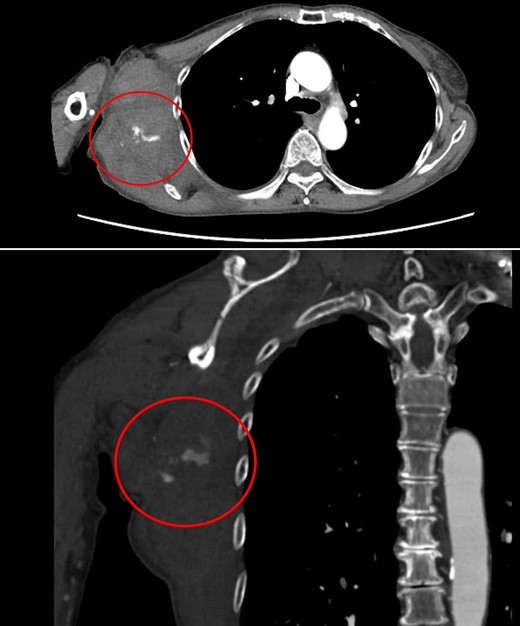

Four days later, the patient was hospitalized for rapidly worsening swelling and pain, and was readmitted with a diagnosis of rebleeding from the chest wall. Physical examination revealed a fist-sized subcutaneous mass on the right side of the chest, with severe pain. Laboratory data indicated anemia (Hb 7.8 g/dl) and no coagulation disorder: % prothrombin time (PT) 115.1%, prothrombin time-international normalized ratio (PT-INR) 0.93, and activated partial thromboplastin time 23.6 s. Computed tomography (CT) at the time of the first hemorrhage showed the hematoma on the right chest and anterior to the scapula (Fig. 2). Contrast-enhanced CT at the time of rebleeding showed an increase in hematoma and extravasation in the peripheral right lateral thoracic artery (Fig. 3). The patient was immediately treated with emergency angiography, which revealed active bleeding from a pseudoaneurysm of the right lateral thoracic artery. Thus, coil embolization was performed (Fig. 4). There were no TAE-related complications and the patient was discharged to home on the fifth hospital day. Oral clopidogrel was resumed and there has been no recurrence of bleeding.

Contrast-enhanced CT at the time of the second bleeding showed growth of the hematoma and extravasation of contrast agent in a branch of the right lateral thoracic artery.